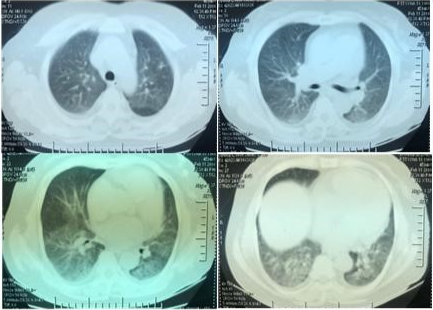

1天前患者劳累后再次出现咳嗽、胸闷不适,来我院就诊,门诊查血常规:WBC 5.3×109L,NEU 59%,Hb 112 g/L,PLT 175×109/L,EOS% 04.3%,  CRP 182.87 mg/ml,胸部CT(图3):两肺纹理增多模糊,两肺野透亮度不均,两肺见弥漫性分布的磨玻璃影,可见小叶结节分布。影像诊断:两肺弥漫性病变,考虑:过敏性肺泡炎?病毒感染?两侧少许胸膜增厚。

图片

图3  胸部CT(2017年11月9日)

注:两肺弥漫性病变,考虑:过敏性肺泡炎?感染(病毒)?心脏稍增大。两侧少许胸膜增厚。纵隔淋巴结稍大。左侧乳腺内结节影,请结合专科检查